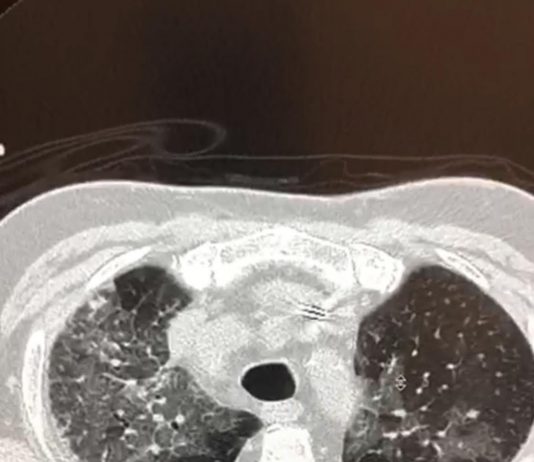

78-year-old patient with fever and cough for 1 week. pO2: 84 %.

CT